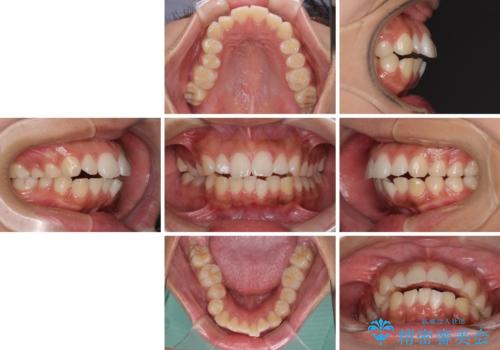

- 出っ歯と口の閉じにくさ、デコボコを気にして来院された患者様です。

口元の突出感を改善するため、上下左右第一小臼歯4本の抜歯を行い、ワイヤー装置による矯正治療を行うこととしました。

舌の突出癖により上下前歯は非接触であり、非常に前方に飛び出している状態でした。

舌のトレーニングをしっかりと行っていただき、口の閉じやすい歯並びに仕上げることができました。